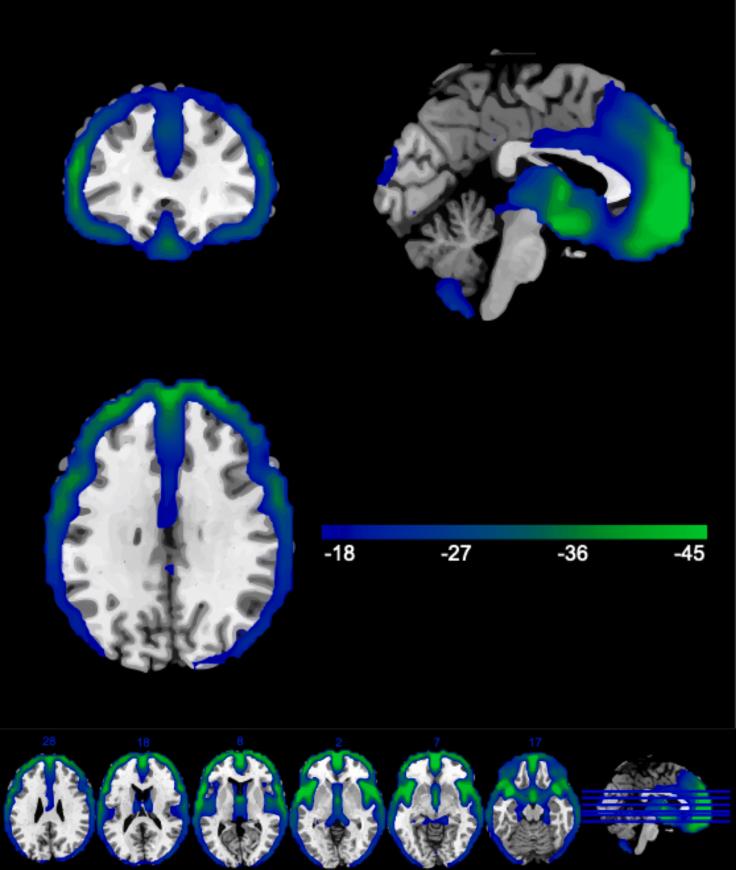

Structural neuroimaging studies have identified a combination of shared and disorder-specific patterns of gray matter (GM) deficits across psychiatric disorders. Pooling large data allows for examination of a possible common neuroanatomical basis that may identify a certain vulnerability for mental illness. Large-scale collaborative research is already facilitated by data repositories, institutionally supported databases, and data archives. However, these data-sharing methodologies can suffer from significant barriers. Federated approaches augment these approaches by enabling access or more sophisticated, shareable and scaled-up analyses of large-scale data. We examined GM alterations using Collaborative Informatics and Neuroimaging Suite Toolkit for Anonymous Computation, an open-source, decentralized analysis application. Through federated analysis of eight sites, we identified significant overlap in the GM patterns ( = 4,102) of individuals with schizophrenia, major depressive disorder, and autism spectrum disorder. These results show cortical and subcortical regions that may indicate a shared vulnerability to psychiatric disorders.

结构神经影像学研究已经确定了跨精神疾病的灰质(GM)缺陷的共享模式和特定疾病模式的组合。汇总大数据有助于检查可能的共同神经解剖学基础,这可能识别出精神疾病的某种易感性。数据存储库、机构支持的数据库和数据档案已经促进了大规模的合作研究。然而,这些数据共享方法可能存在重大障碍。联邦方法通过实现对大规模数据的访问或更复杂、可共享和可扩展的分析来增强这些方法。我们使用用于匿名计算的协作信息学和神经影像学套件工具包(一种开源、去中心化的分析应用程序)检查了灰质改变。通过对八个站点的联邦分析,我们在精神分裂症、重度抑郁症和自闭症谱系障碍患者的灰质模式(n = 4102)中发现了显著重叠。这些结果显示了可能表明对精神疾病存在共同易感性的皮质和皮质下区域。